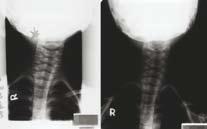

有醫學研究報告指,約每1,000人中有2人患有脊柱側彎,但成因不明,不過也有很大機會由於成長時脊骨骨骼及鄰近肌肉的生長速度不一致而引起。此症常見於11至15歲的女孩,每4名患者中只有1人是男,而如果及早發現有此現象,在發育中還有很大的機會改正。治療包括伸展運動、姿勢糾正及使用矯形器。至於現代學生書包重,以及經常使用電腦,也有機會令本來的脊柱側彎問題惡化。(圖四,右為脊柱側彎)

圖四